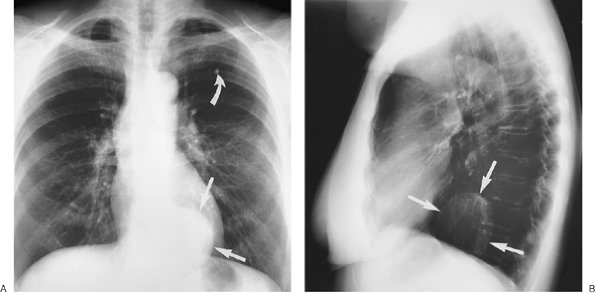

FIGURE 6-25. Sarcoidosis. PA (A) and lateral (B) chest radiographs of an asymptomatic 25-year-old man show bilateral hilar adenopathy (straight arrows). The enlarged nodes are potato shaped and clear of the cardiac borders, a feature that can help distinguish them from lymphomatous enlargement of hilar nodes. On the lateral view, subcarinal adenopathy is also seen (curved arrows).

Sarcoidosis is a frequent cause of intrathoracic adenopathy in young adults. When multiple node groups are involved and adenopathy is symmetrically distributed in the hila and mediastinum in young asymptomatic adults, sarcoidosis is the likely cause. The hilar lymph nodes are frequently potato shaped and clear of the cardiac borders, a feature that is often useful in distinguishing sarcoidosis from lymphoma (Fig. 6-25).

Enlargement of paratracheal and bilateral hilar lymph nodes (the Garland triad, or the "1-2-3 sign") is a nonspecific pattern of adenopathy that is common in patients with sarcoidosis (Fig. 6-26).